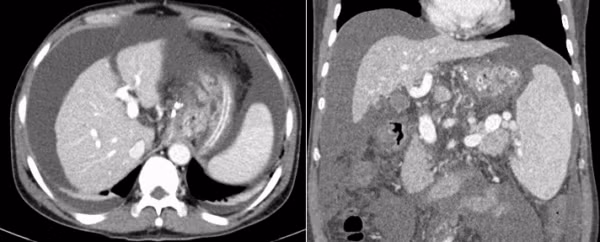

Hình ảnh xơ gan và dịch ổ bụng mức độ nhiều trên phim chụp cắt lớp vi tính của người bệnh - Ảnh BVCC

Tuy nhiên, do tình trạng giãn tĩnh mạch thực quản nhiều và kích thước lớn nên người bệnh được đánh giá có nguy cơ chảy máu tái phát rất cao. Cùng với đó, người bệnh có tình trạng chướng bụng nhiều do dịch tự do trong ổ bụng.